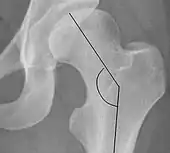

Cervical diaphyseal angle The angle formed between the femoral neck and femoral diaphysis 120° to 140°

• Higher indicates coxa valga

• Lower indicates coxa vara